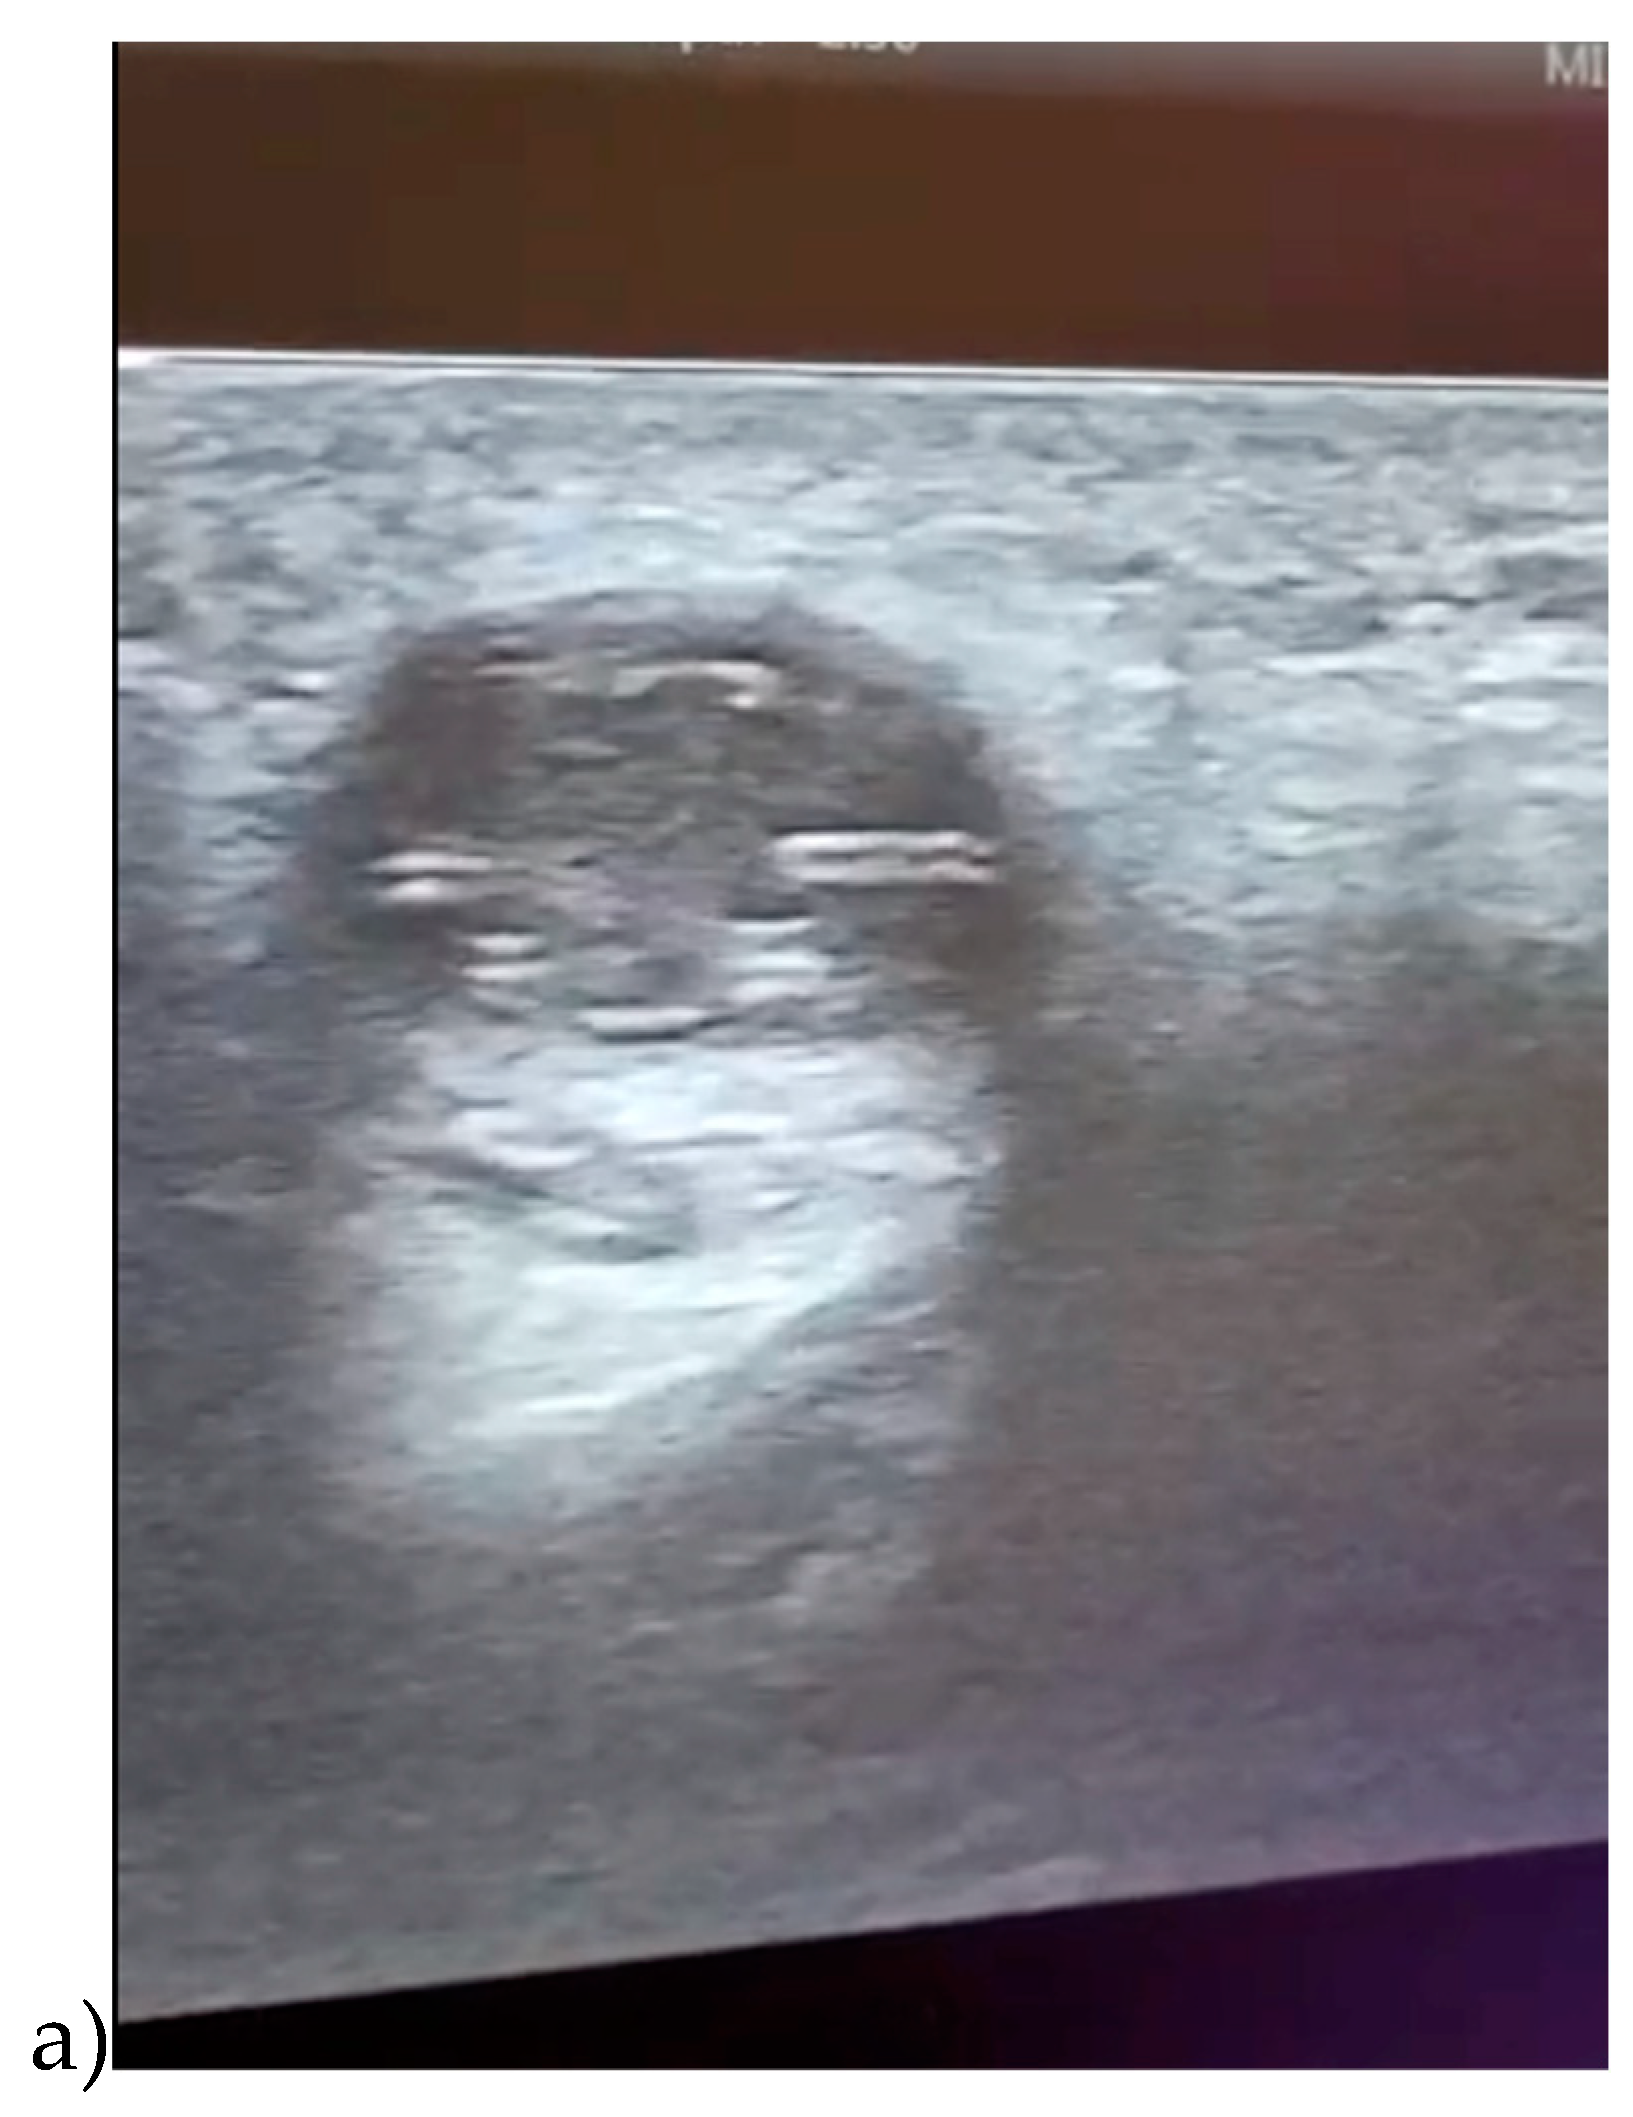

No cervical or general limphadenopathy was detected. Through ultrasound scanning of the genian region was detected a well-defined round hypoechogenic lesion that included a moving tubular structure with a length of 10mM and a width of 1mM (Figure 3 and Figure 4).

Figure 3. a,b. Ultrasound image of the genian region showing a cystic mass including a motile tubular structure in different positions: a) position 1; b) position 2.